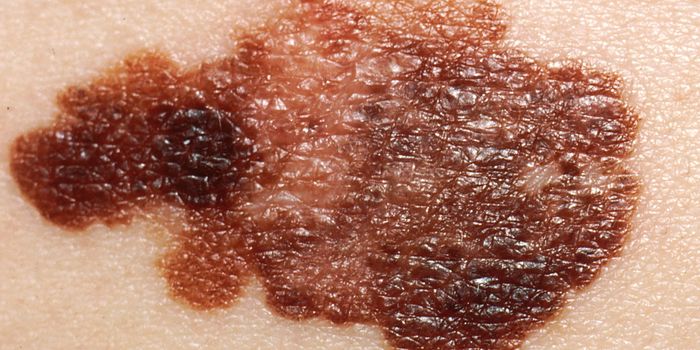

AUG 30, 2017CancerThe next time you inspect your body for signs of skin cancer, pay special attention to new moles that were not there the ...